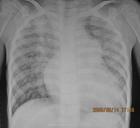

檢查肺心病

胸片右圖示慢性氣管炎,肺氣腫,肺心病。雙側肺過度充氣,

肋間隙增大,

雙肺紋理粗大,

心臟呈垂滴形。

肺動脈段突出。